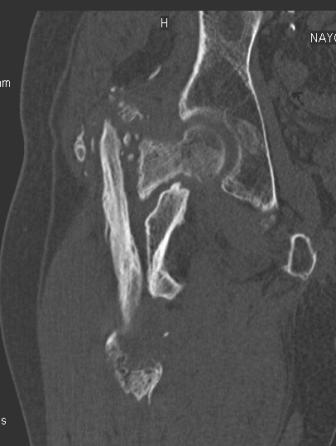

[Ortho] Сросшийся со смещением чрез-подвертельный перелом

Вложение не в текстовом формате было извлечено…

Имя     : уменьш (7).jpg

Тип     : image/jpeg

Размер  : 17100 байтов

Url     : http://weborto.net:8080/pipermail/ortho/attachments/20091031/f055a08c/attachment-0007.jpg